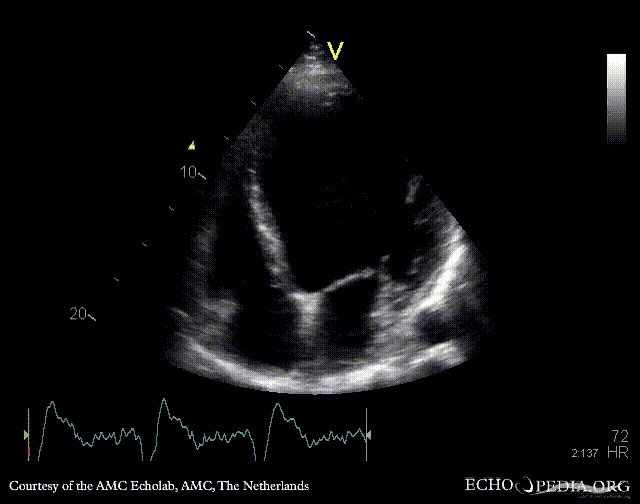

Dyssynchronie of left ventricle

A4CH: dyssynchronie in contraction of left ventricle